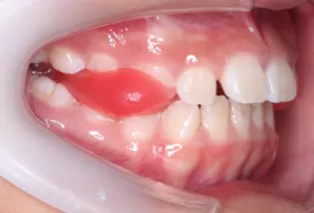

Intraoral photos